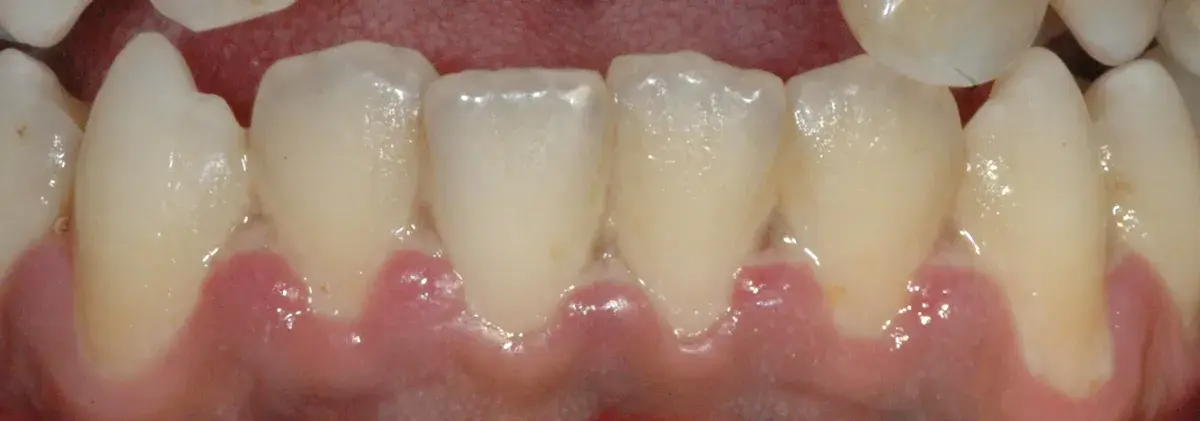

Cresta atrofica in zona 4.6 con difetto osteo-mucoso e cheratinizzata quasi assente: Bonebending 4.0 e impianto in unica seduta. Risultato a 3 mesi.

Perché le gengive si ritirano, quando preoccuparsi e cosa può fare il parodontologo. Classificazione di Cairo, innesto connettivale, lembo coronale.

Tecniche di sutura e gestione della gengiva cheratinizzata attorno agli impianti. Perché la qualità dei tessuti molli è cruciale per la longevità implan...

Le recessioni gengivali possono essere corrette o meno. Esistono indicazioni assolute e relative al trattamento chirurgico con copertura radicolare.